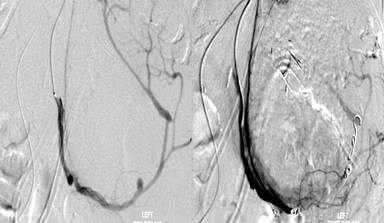

Unfortunately, she was admitted two weeks later with fever, melena and coffee ground vomiting. Her blood pressure was 80/50 mmHg, pulse was 120 beat per minute and her hemoglobin dropped to 7.6 g/dL. EGD revealed massive blood clots in the stomach and although the stent was in situ, there were clots seen within the stent which suggested that the source of bleeding was from the cystic cavity. She was referred for angiography and embolization; angiogram showed bleeding from a ruptured splenic artery pseudoaneurysm. Coil embolization (Figure 5) was carried out successfully and patient’s vital signs improved immediately. She was discharged well a few days later.

Figure 5. Angiography showing splenic artery pseudoaneurysmal bleed (left) followed by coil embolization (right). |